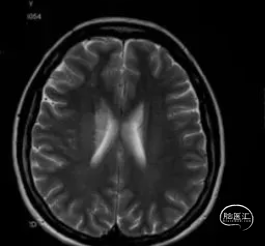

2024-05-24 MRI示右侧基底节区梗塞灶

2024-08-19 入院查MR未见新发梗死灶